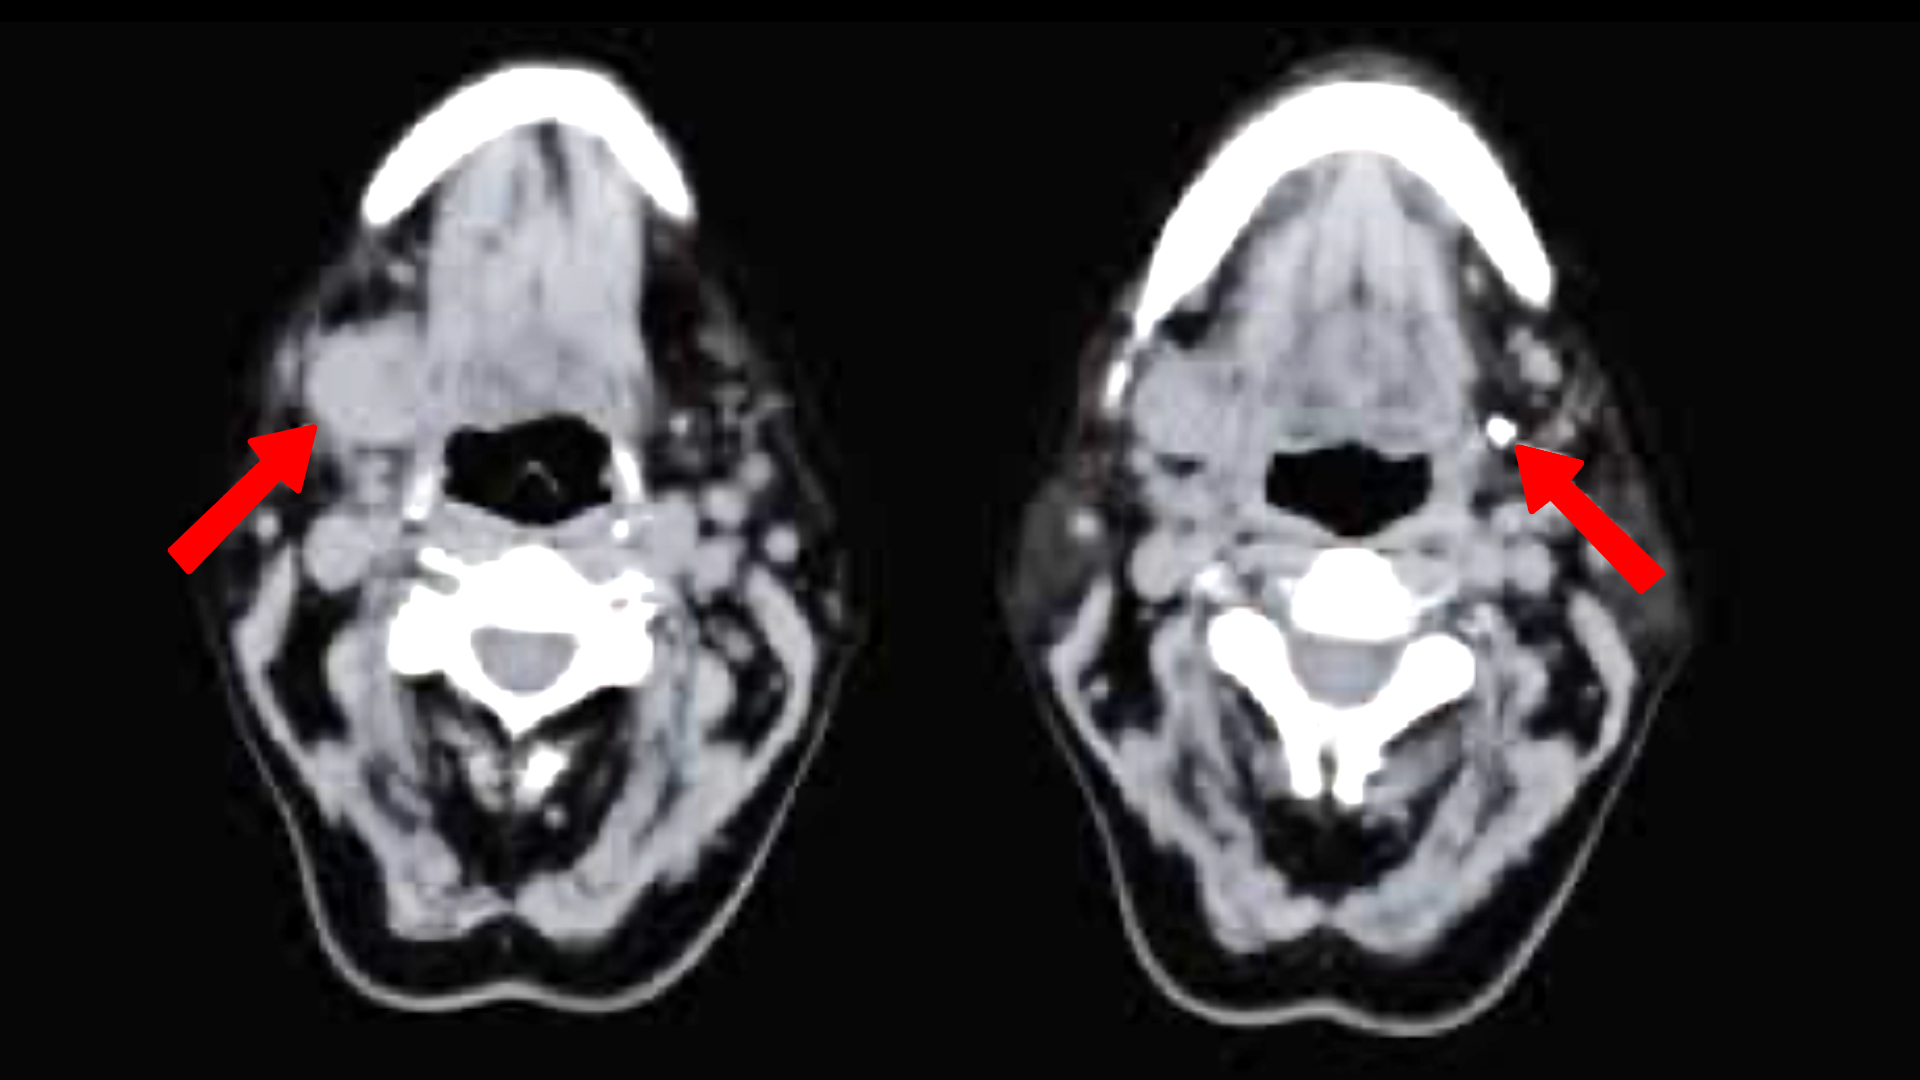

Η απεικόνιση ανήκει στην προετοιμασία μιας επέμβασης. Τις περισσότερες φορές είναι μία ή περισσότερες εικόνες υπερήχων του αδένα που πρέπει να χρησιμοποιηθούν. Σε ορισμένες περιπτώσεις απαιτείται τομογραφία (MRI, CT).